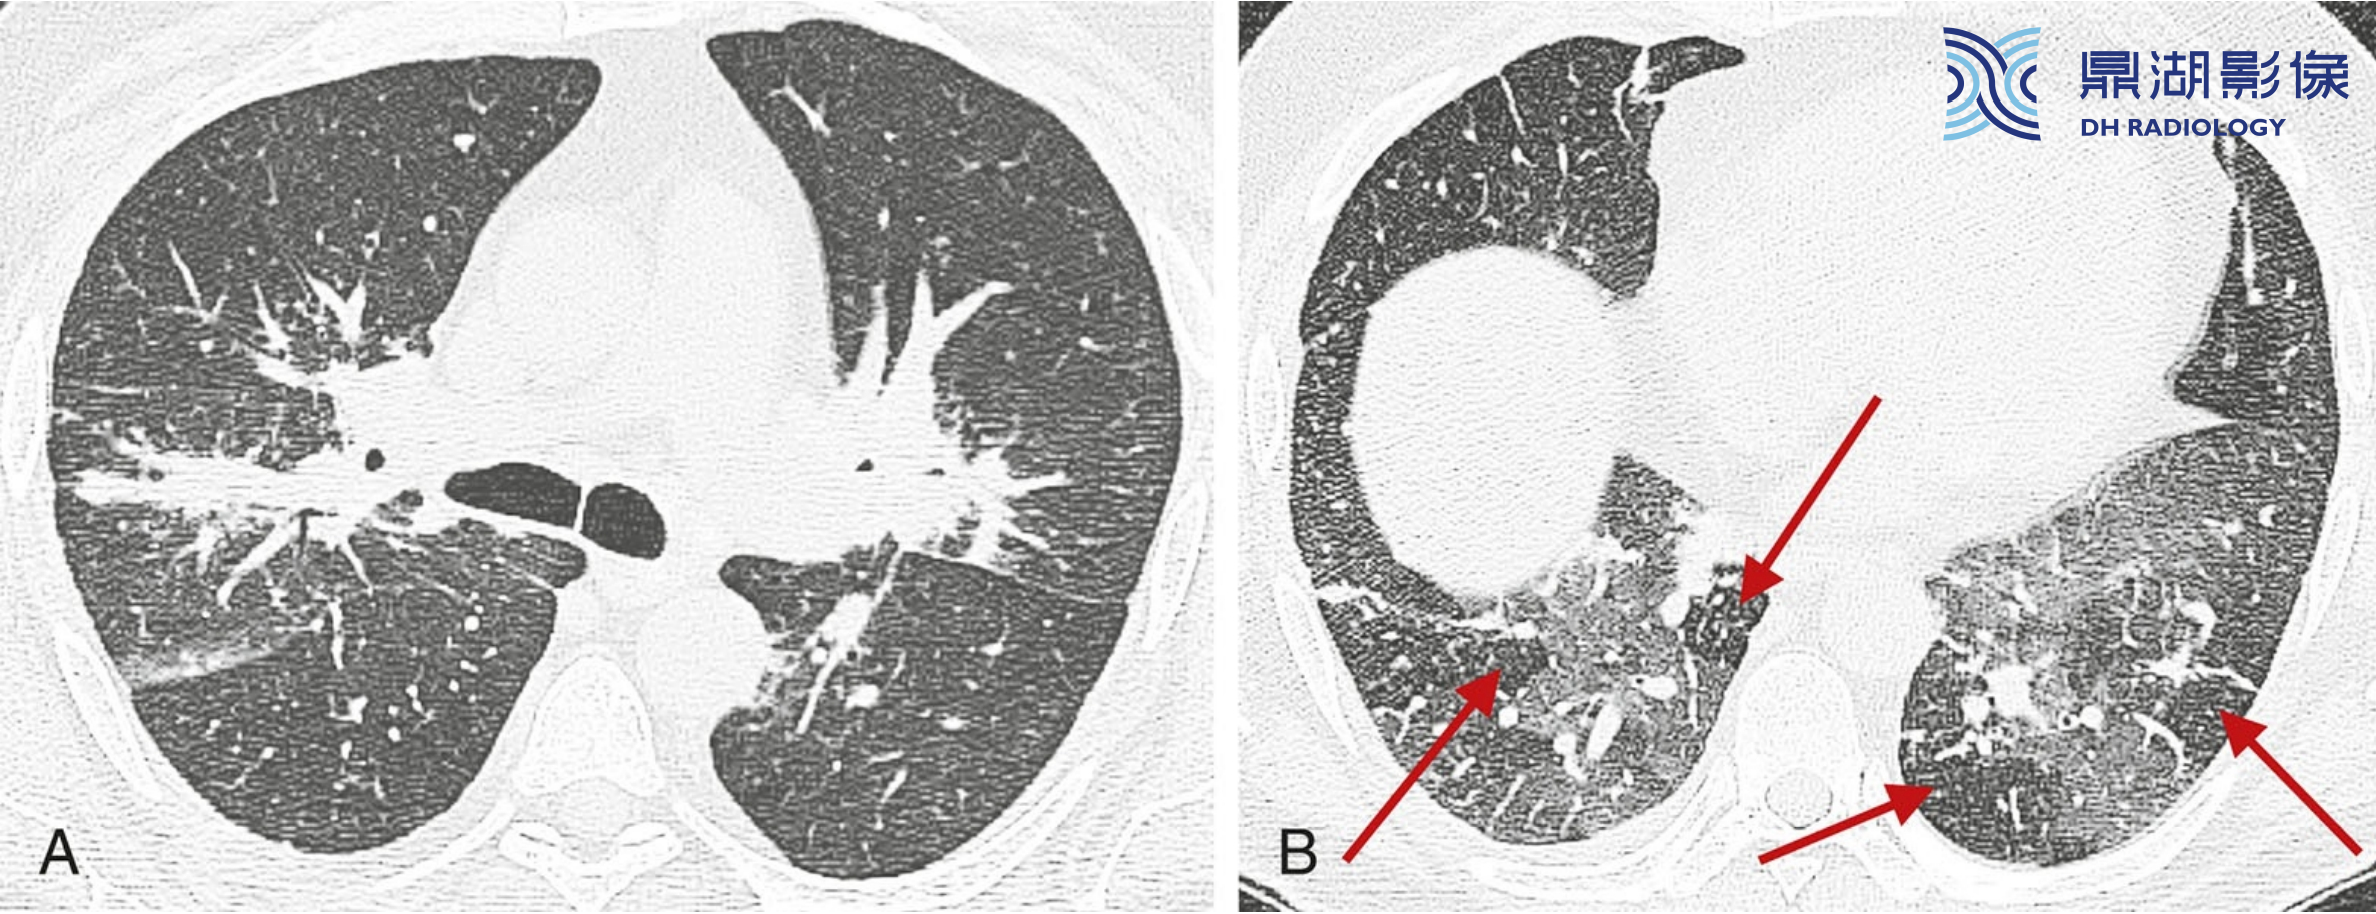

a6e40d7ee5c68dbaf183e07ee5edee07.jpg

结节病的典型表现。

A至C广泛累及肺部的结节病患者,HRCT可见簇状和团块样结节,包绕肺门的动脉、支气管及支气管血管周围间质(红箭,B), 分布于外周支气管血管周围(红箭,A和C) 、肺外周及与叶间裂相邻的胸膜下间质(蓝箭)。